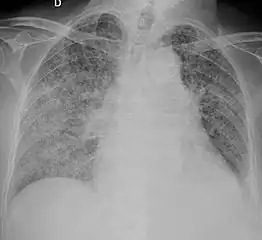

X-ray, showing extensive bilateral reticulo-nodular infiltrates